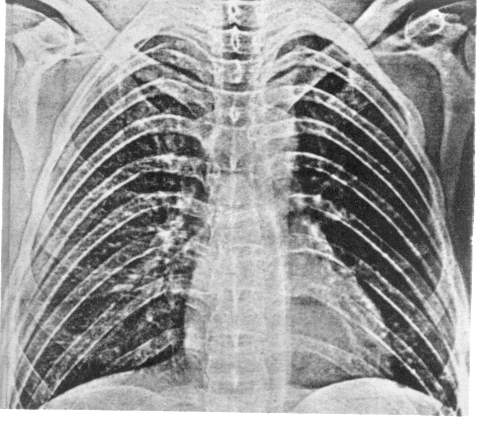

Рис. 3. Рак верхней доли левого легкого.

а — прямая рентгенограмма: б — боковая рентгенограмма.

Последующее рентгенографическое обследование должно углублять и расширять представления о характере изменений в легких и грудной полости. Эти исследования проводят в прямой (переднезадней) и боковой проекциях, дополняя их при необходимости снимками в косых проекциях и прицельными рентгенограммами (рис. 1). Важным достоинством рентгенографии являются объективность и достоверность полученных результатов, возможность сопоставления с данными ранее проведенных рентгенографических обследований, т. е. возможность динамического наблюдения. Последнее нередко является одним из важнейших факторов для установления правильного диагноза.

Рентгенографическое обследование в двух проекциях позволяет с наибольшей точностью определить локализацию и распространенность поражения легких, изменения в средостении, состояние междолевых щелей, оценка и сопоставление степени прозрачности участков легкого в различных его отделах, мельчайшие очаговые тени, что особенно ценно при проведении дифференциального диагноза между туберкулезом легких, саркоидозом, пневмокониозом и другими заболеваниями, дающими исходные рентгенологические изменения.